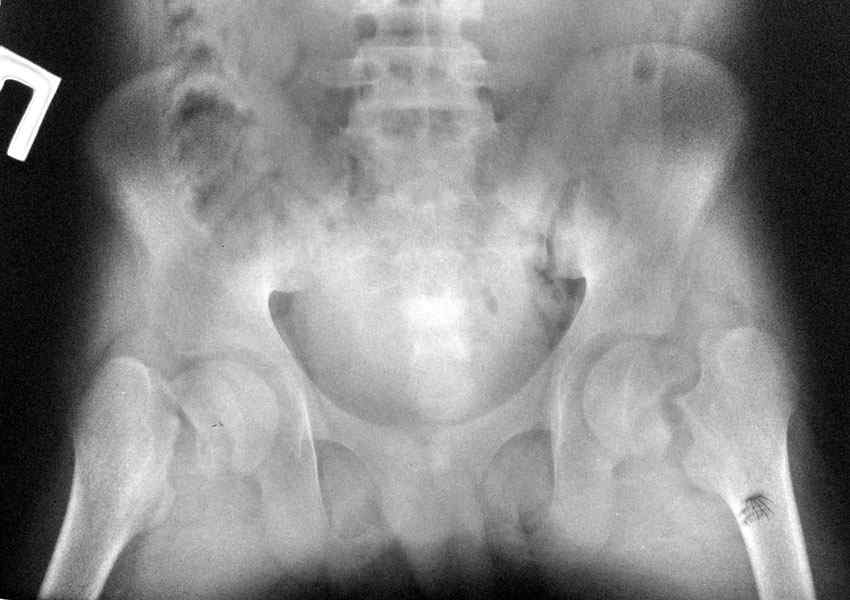

ренальная остеодистрофия и двусторонний перелом шеек бёдер |

Больной 14 лет с врождённой аномалией развия почек. Уретрогидронефроз справа. Вторично сморщенная почка.ХПН терминальная стадия. На фоне гемодиализа двусторонний трансцервикальный перелом бёдер.

В течении 6 мес. по настоящее время скелетное вылежение по м.ж. в областном городе. В настоящее время проводится терапия в составе: гемодиализ 3,5 часа 3 раза в неделю, Кальций Д3 никомед, Альфа Д3 0,25 мкг ежедневно,+ терапия вторичной гипертензии. Непростая ситуация, Уважаемые коллеги, у кого, какое мнение по этому поводу? Пулатов А.Р. УНИИТО